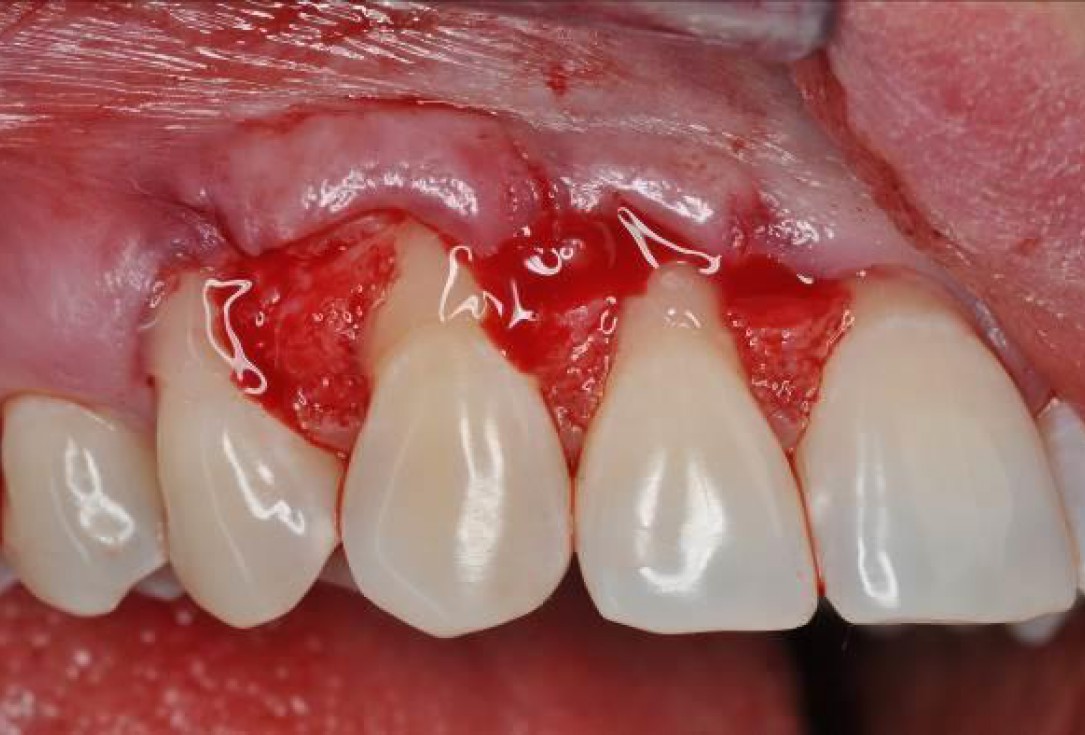

03/06 - Application of Straumann® Emdogain® to the root surfaces.Multiple gingival recessions treated with the modified coronally advanced flap in conjunction with mucoderm® and Straumann® Emdogain® - Dr. D. B. Hangyási